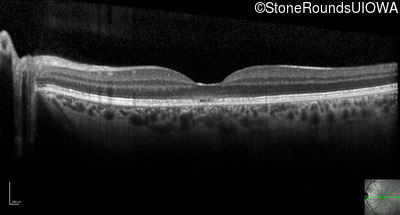

Optical Coherence Tomography - Right - 20/63 +2 sc

Exemplar / OCT Stack